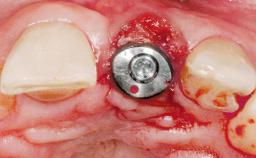

Immediate Placement of an Implant in a Maxillary Right Central Incisor Site

A 30-year-old female patient was referred to the office for the treatment of tooth 11. Her chief concern at the initial visit was to inquire, “Why is my tooth pink?” Upon clinical examination, it was determined that tooth 11 had a previous history of trauma and that the clinical crown had become noticeably pink in color as a result of internal resorption. This diagnosis was confirmed radiographically, indicating a large radiolucency involving the central and distal portions of the clinical crown. It was determined that restoration of this tooth was not possible, and that extraction was indicated. The presence of a mid-line diastema, which the patient wanted to reproduce, directed the treatment plan for tooth replacement utilizing a dental implant.

Socket Integrity Sufficient, with intact bone walls

Bone Volume Sufficient, with intact walls

Esthetic Risk High